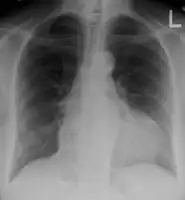

- A pericardial effusion as seen on CXR in someone with pericarditis